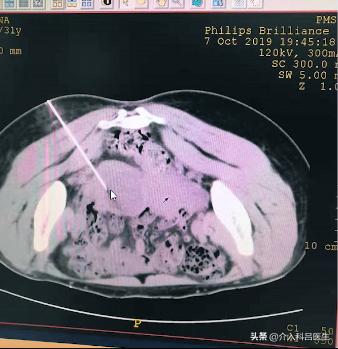

图是CT的图像,在臀部扎针进来,把里面的囊液抽出来。我没有照囊液的图片,囊液有一百多毫升,全是那种粘稠的血性的。

抽出囊液后,我们打酒精硬化。图可以看到巧克力囊肿没了,就剩这么一点了,这是超级微创的一个治疗方法。